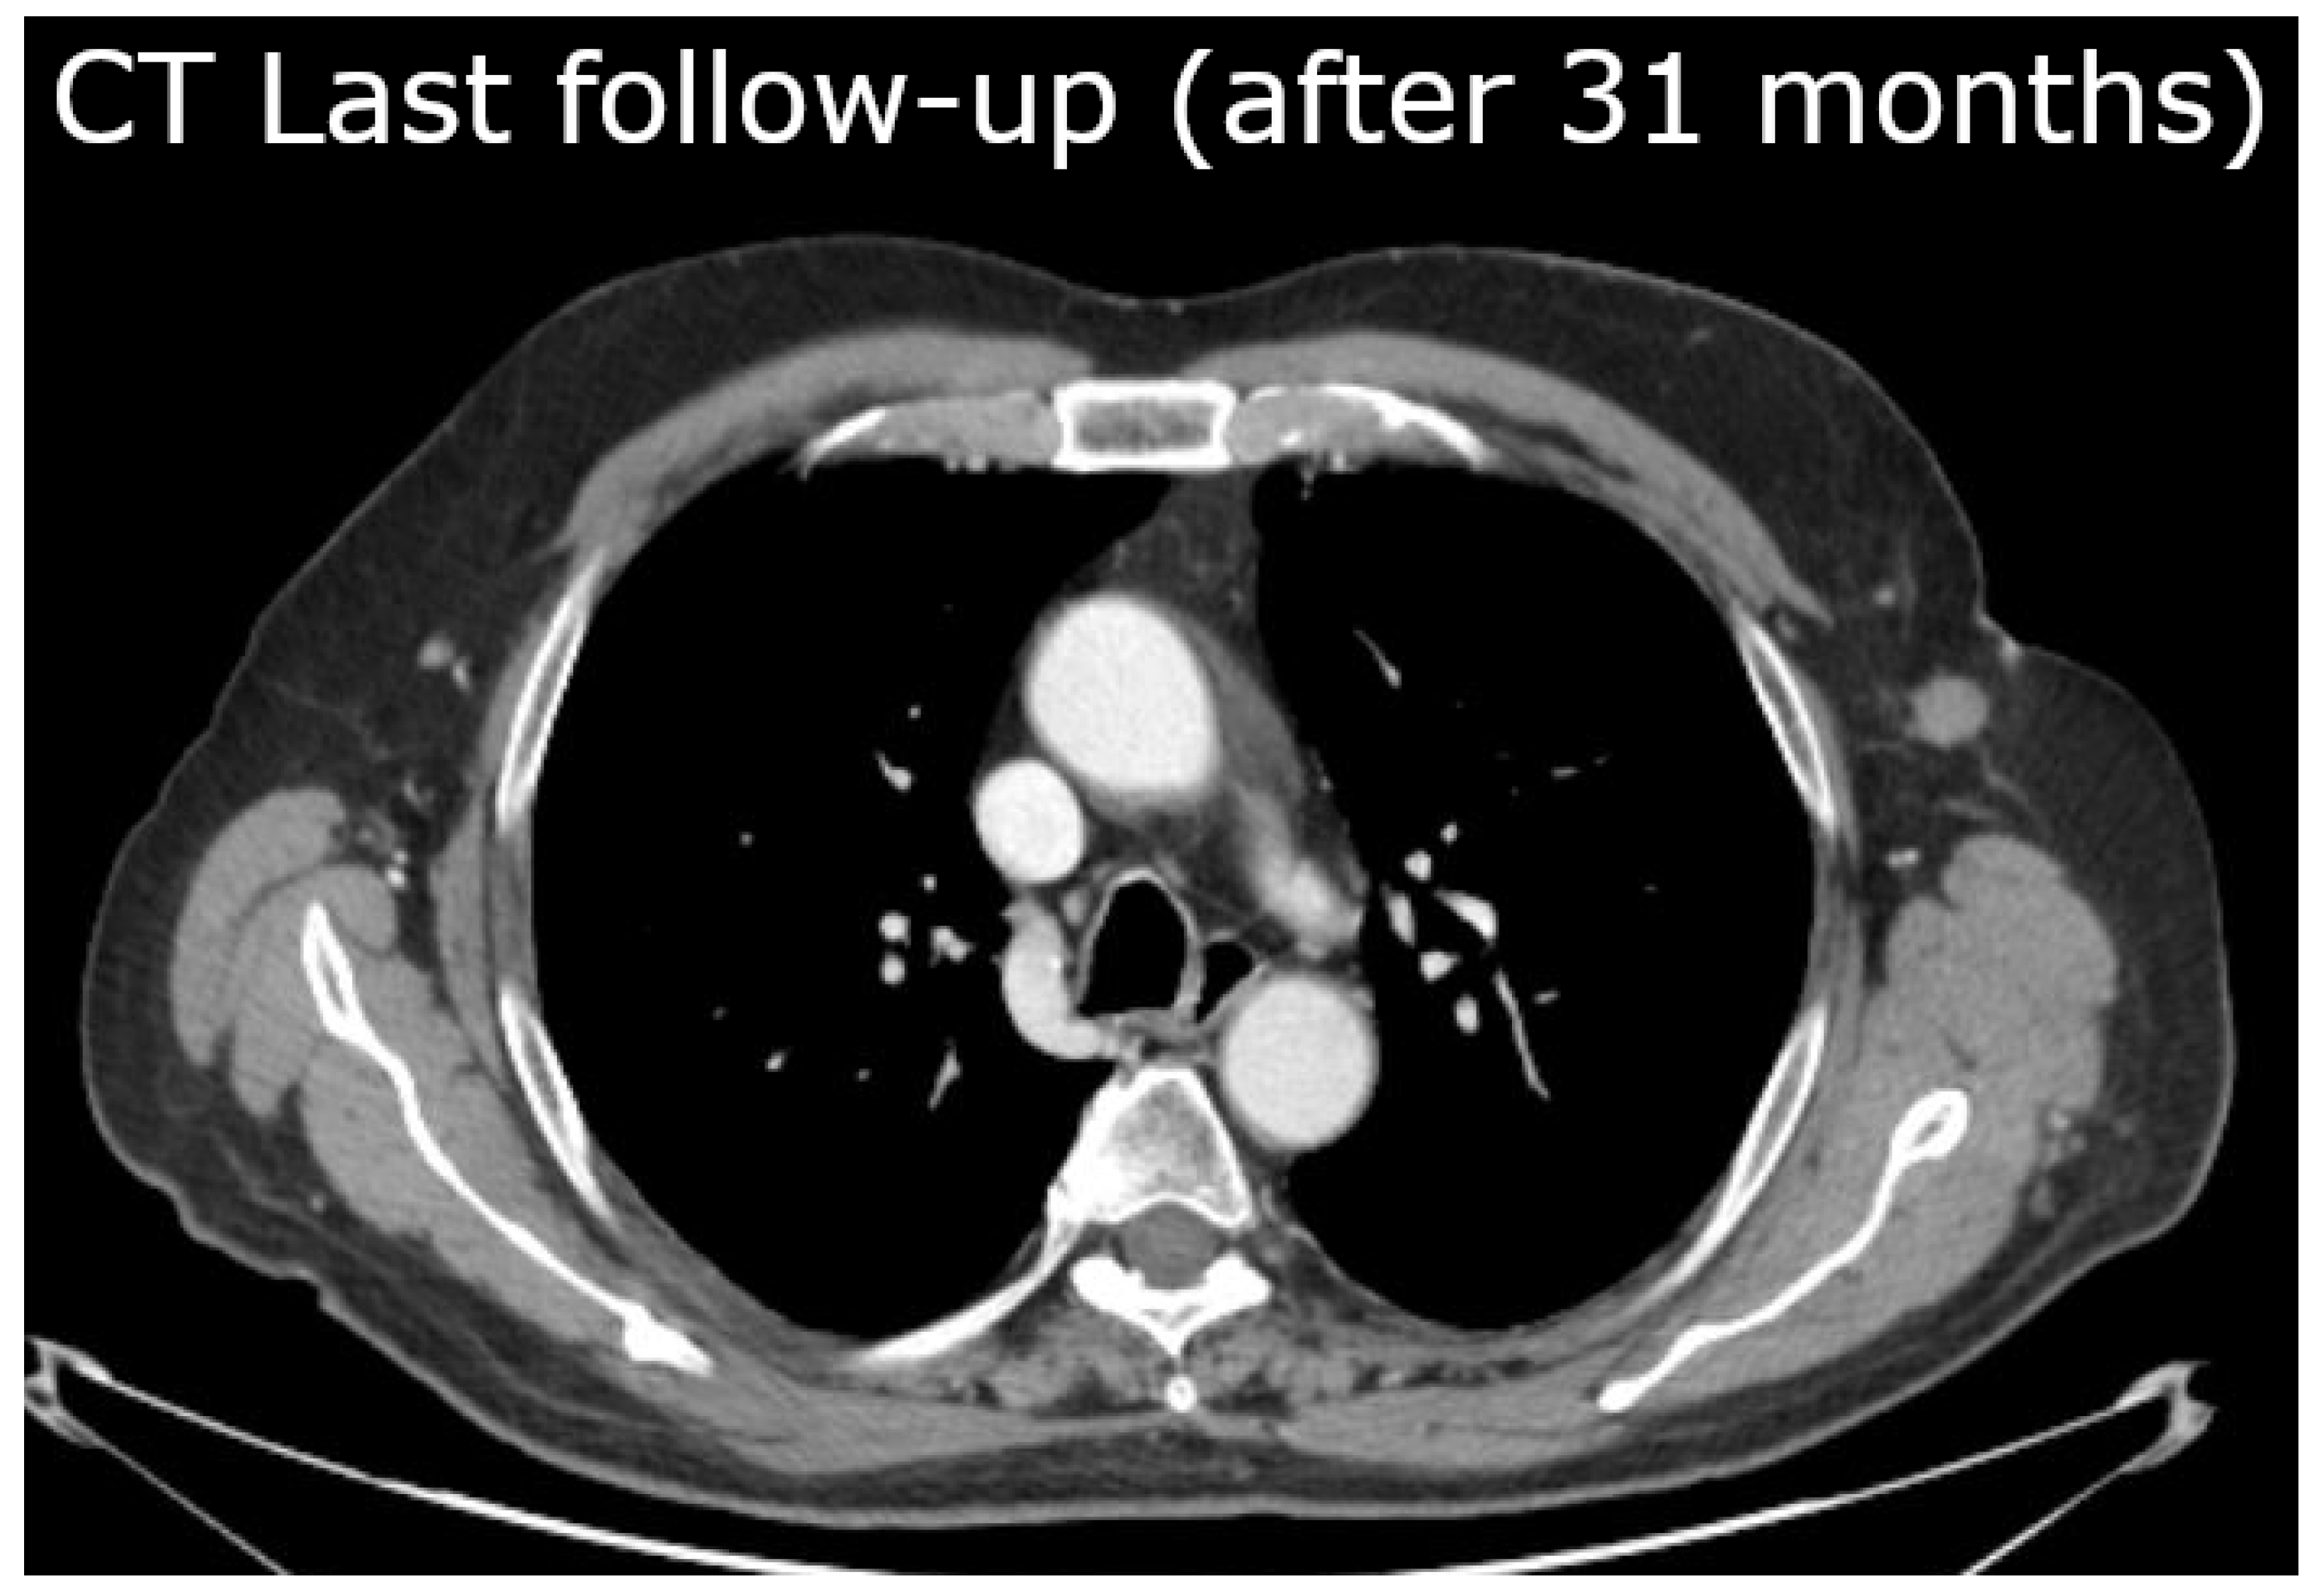

2. The Case Report: Radiotherapy and Clinical Results

4. Application to the Case Report